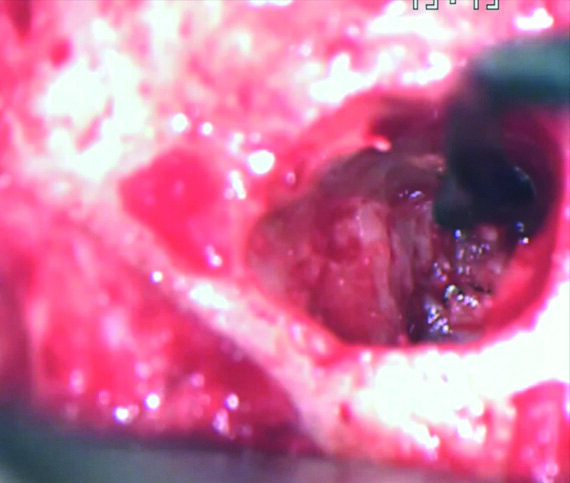

Le plan de traitement a consisté à tenter de résoudre le problème par une approche classique et, au besoin, par une microchirurgie, en vue de conserver la dent. J’ai pu retirer le cône de la racine palatine a l’aide de limes H (Hedstrom) mais il était impossible de contourner les fragments de lime présents dans la racine mésiale, ou même de les atteindre avec des inserts ultrasoniques. Je me suis résolu à ne pas en faire trop afin de ne pas créer un nouveau problème, tel qu’une perforation de la paroi canalaire, et j’ai décidé de sceller les canaux (Fig. 10). La décision de traiter les canaux mésiaux par une approche chirurgicale a été prise immédiatement. J’ai sectionné 3 mm de la racine mésiale à l’aide d’une pièce à main Impact Air (SybronEndo), ce qui m’a donné une vue directe sur la membrane de Schneider, de laquelle le troisième fragment dépassait à peine (Figs. 11 et12). Je suis parvenu a le saisir délicatement et à l’extraire (Fig. 13). La figure 14 montre la situation post-opératoire, après la fin de la préparation à retro des canaux mésiaux.